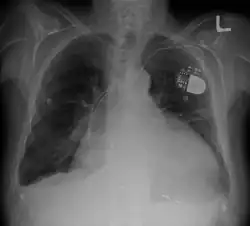

Cardiomegaly on chest X-ray with a pacemaker

• Chest X-ray: X-ray images help to visualize the condition of the lungs and heart. If the heart is enlarged on an X-ray, other tests will usually be needed to find the cause. A useful measurement on X-ray is the cardio-thoracic ratio, which is the transverse diameter of the heart, compared with that of the thoracic cage.[30] These diameters are taken from PA chest x-rays using the widest point of the chest and measuring as far as the lung pleura, rather than lateral skin margins. If the ratio is greater than 50%, pathology is suspected.[31] The measurement was first proposed in 1919 to screen military recruits. A newer approach to using these x-rays for evaluating heart health takes the ratio of heart area to chest area and has been called the two-dimensional cardiothoracic ratio.[32]